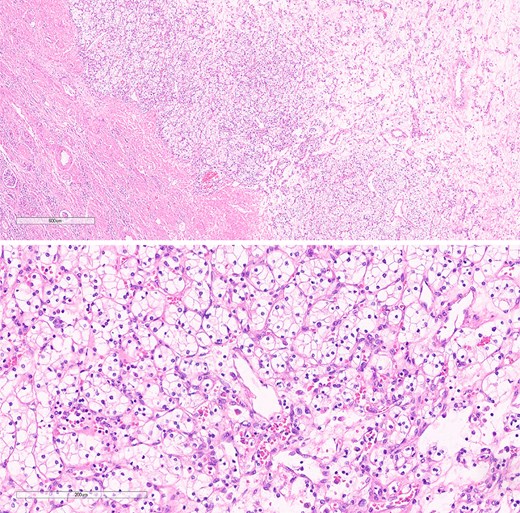

Histopathological specimens of the kidney revealed clear cell RCC (ccRCC) (Fig. 5), measuring 4.0 × 4.0 × 3.8 cm with a histologic grade of G2. The tumor growth was limited to the kidney, with all margins negative for invasive carcinoma. Tumor necrosis was present at 10%. Lymphovascular invasion was present. This case of RCC was staged as T1aN0M0 according to the TNM classification [8]. The sigmoid colon mass analysis revealed low-budding, well-differentiated adenocarcinoma, size 6.5 cm, with submucosal invasion (T1). There is no lymphovascular or perineural invasion. The margin was negative for both proximal and distal mesenteric margins. The remaining tissue examination revealed a tubular adenoma with focal high-grade dysplasia. There were negative results for metastatic carcinoma in all 12 lymph nodes from the specimen. In this case, the TNM staging for the sigmoid colon carcinoma was determined to be T1N0M0 [9].

The histological section of RCC shows clear cytoplasm and cellular morphology consistent with clear cell RCC.